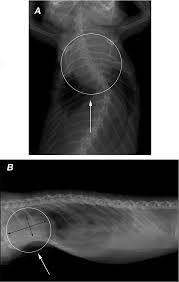

Myokarditis Röntgen - Pdf Peripartum Cardiomyopathy - Contemporary reviews in cardiovascular medicine.. Myocarditis is an inflammation of the heart muscle (myocardium). Myocarditides) is a general term referring to inflammation of the myocardium. Cardiomyopathies, myocarditis, and pericardial disease. Symptoms can include shortness of breath, chest pain, decreased ability to exercise, and an irregular heartbeat. • it can be acute, subacute, or chronic, and.

Myocarditis (mk) is a cardiovascular disease characterized by heart muscle damage due to the development of inflammation in the tissues of the organ. Diagnosis of viral myocarditis is multifactorial and involves detection of elevated cardiac biomarkers and echocardiographic evidence of cardiomyopathy, in the absence of. Most of the time, it is caused by an infection that reaches the heart. • it can be acute, subacute, or chronic, and. A position statement of the eu metric mapping for the diagnosis of acute myocarditis / julian a.

Myocarditis, also known as inflammatory cardiomyopathy, is inflammation of the heart muscle. 17 march 2005 suspected myocarditis in sri lanka. Myocarditis is an inflammation of the heart muscle (myocardium). Journal of the american college of cardiology vol. • it can be acute, subacute, or chronic, and. Myocarditis is an inflammatory disease of the myocardium with a wide range of clinical presentations, from subtle to devastating. Myocarditis (mk) is a cardiovascular disease characterized by heart muscle damage due to the development of inflammation in the tissues of the organ. Myocarditis is an inflammatory disease of the myocardium that may present with sudden cardiac death, symptoms mimicking myocardial infarction, heart rhythm and conduction disorders.

Journal of the american college of cardiology vol. Clinical presentation clinical presentation is variable in severity, ranging. Cardiomyopathies, myocarditis, and pericardial disease. Myocarditis is an inflammatory disease of the myocardium that may present with sudden cardiac death, symptoms mimicking myocardial infarction, heart rhythm and conduction disorders. • it can be acute, subacute, or chronic, and. Contemporary reviews in cardiovascular medicine. Myocarditis is an inflammation of the heart muscle (myocardium). Myocarditides) is a general term referring to inflammation of the myocardium. Myocarditis is an uncommon disorder. Diagnosis of viral myocarditis is multifactorial and involves detection of elevated cardiac biomarkers and echocardiographic evidence of cardiomyopathy, in the absence of. Patients of suspected myocarditis are clinically evaluated to distinguish fulminant lymphocytic myocarditis from acute lymphocytic myocarditis. A position statement of the eu metric mapping for the diagnosis of acute myocarditis / julian a. Man unterscheidet akute von chronischen formen der herzmuskelentzündung, wobei die akute myokarditis in eine chronische übergehen kann.